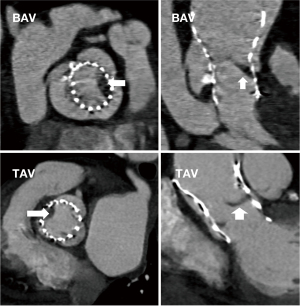

As shown in Figure 1, a total of 748 patients underwent TAVR for severe aortic stenosis at West China Hospital between May 2012 and January 2021. After the inclusion and exclusion criteria were applied, 605 patients were included in the final analysis. Baseline characteristics, procedural details, in-hospital clinical outcomes, and post-TAVR echocardiographic data were collected for these patients. The average age of patients was 73.97±6.88 years, with 340 (56.2%) being male. The average Society of Thoracic Surgeons (STS) score (16) was 6.43%±4.52%. The patients were divided into two groups based on the presence or absence of HALT observed on CT scans at discharge. Figure 2 illustrates the typical findings of HALT on CT in patients with BAV and TAV. HALT was detected in 13.1% (n=79) of patients during hospitalization (HALT group), while the remaining 526 patients did not develop HALT (non-HALT group). In the HALT group, 38 (48.1%) patients were male, while 302 (57.4%) were male in the non-HALT group. The average age of patients in the HALT group was 75.53±6.44 years, while that in the non-HALT group was 73.73±6.91 years. The HALT group had a higher proportion of patients with BAV. Patients in the non-HALT group had a higher body mass index (BMI), while the HALT group exhibited a higher incidence of coronary artery disease (CAD) and aortic regurgitation. A more detailed comparison of the baseline characteristics between the two groups is provided in Table 1.

Multislice computed tomography (MSCT) acquisition and analysis

All MSCT scans were performed with a second-generation dual-source CT system (SOMATOM Definition Flash; Siemens Healthineers, Erlangen, Germany) and were contrasted prior to and following TAVR, as previously described (14). The annulus type was determined preoperatively with FluoroCT 3.0 software (Circle Cardiovascular Imaging Inc., Calgary, Canada). The identification and determination of HALT were in line with those of previous studies (10,15), with further assessment of leaflet motion being omitted due to data limitations. The presence of a hypoattenuating mass attached to bioprosthetic cusps or diffuse thickening of more than one cusp identifiable in at least two different multiplanar reformatted reconstructions projections was individually assessed by two investigators (6). Disagreements were settled via consultation with a third senior physician.